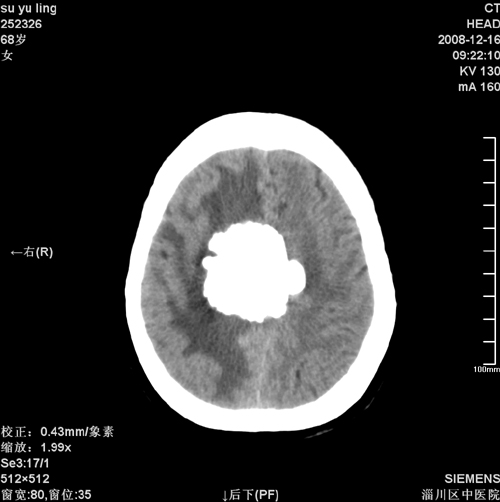

女,68岁,左侧肢体活动不利。

病灶比较均匀钙化,水肿明显,紧贴颅顶与大脑镰并跨越大脑镰----支持脑膜瘤

脑袋里长核,少见。支持脑膜瘤钙化考虑。

1)考虑镰旁脑膜瘤钙化。2)小脑萎缩。

头一次看到这么大钙化脑膜瘤,且其周水肿范围太大